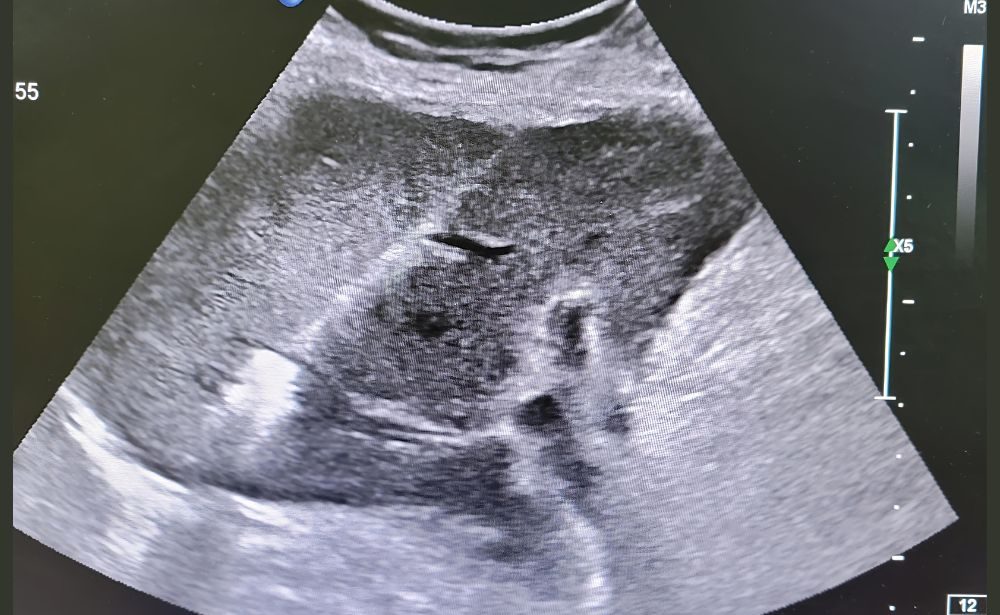

Our Solution: Under precise CT or Ultrasound guidance, a thin probe is inserted directly into the tumor. The tip then emits either radiofrequency (heat) or microwave energy, completely destroying the cancerous cells in a controlled zone.